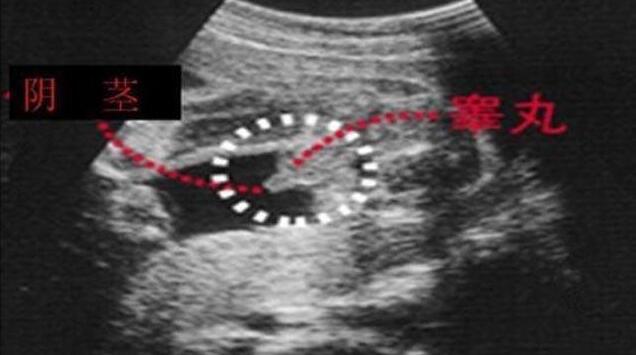

男宝宝如何通过B超分辨出来呢,其实也很简单了,如果角度合适,男宝的B超图上是可以看到小丁丁的。下图拍摄取的角度就是宝宝屁屁正下方,一目了然。

小丁丁